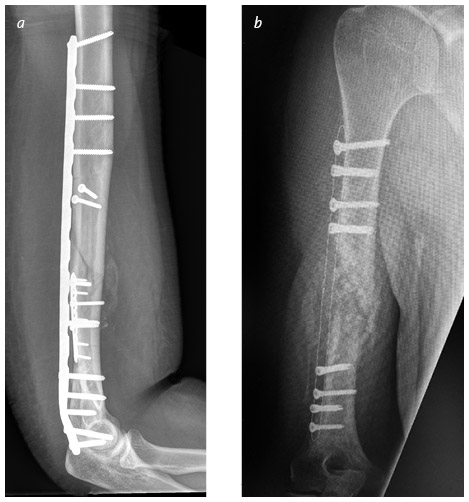

Для изготовления ортопедических пластин и винтов – как стандартных, так и индивидуальных – мы научимся применять различные неметаллические материалы, в том числе легкое, прочное углеродное волокно. Оно рентгенопрозрачное, поэтому рентгеновские лучи проходят сквозь такие имплантаты, не создавая теней, что позволяет полностью визуализировать перелом даже под пластиной.

Иллюстрация к книге — Кости: внутри и снаружи [i_044.jpg]

Традиционные пластины из нержавеющей стали, длинная и короткая, фиксируют множественные переломы плечевой кости (a). Аналогичный перелом с инновационной пластиной из углеволокна, закрепленной обычными металлическими винтами. Пластина не задерживает пучок рентгеновских лучей и заметна только благодаря тонкой стальной проволоке по краям (b)

Clifton Meals, MD (a); Alidad Ghiassi, MD (b)